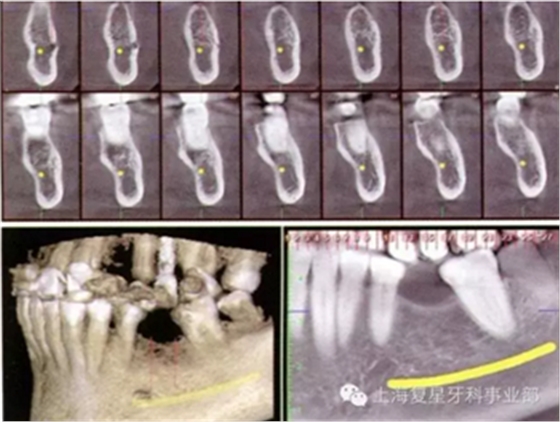

圖3a:左側(cè)下頜骨區(qū)CBCT掃描

一位55歲的健康女性,要求進行下頜磨牙的修復(fù)。她的主訴是:左側(cè)下頜第一磨牙(36#牙)由于幾年前根管治療失敗而拔除導(dǎo)致磨牙缺失。經(jīng)過包括臨床和圖片分析的完整診斷評估后,使用ProMax(普蘭梅卡;圖1和3a)三維掃面儀對左邊的下頜骨進行了CBCT掃描。